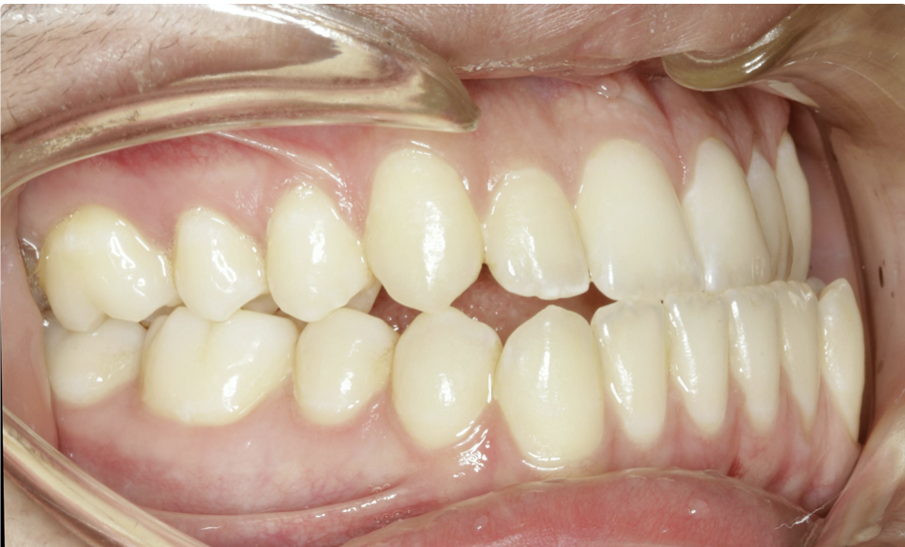

A great solution for Class III patients in need of mandibular distalisation for profile aesthetics and dental function is buccal shelf TADs. This solution allows for noncompliance correction of Class III cases with decreased compensation of the maxillary arch (Figs. 42–45, beginning of treatment). For these cases, a 2 × 12 mm Ortho Bone Screw is placed mesial to teeth #47 and #37 into the buccal shelf of the mandibular body. If the patient has mandibular third molars, then they are extracted right before the TADs are placed once in the stainless-steel wires.

Once the patient has progressed to stainless-steel wires, buccal shelf TADs are placed. A mandibular pre-posted stainless-steel wire is used, and a VectorTAS NiTi closing spring is placed from the buccal shelf TAD to the post (Fig. 46). Once the Class III has been corrected, a steel ligature is used to retain the Class III malocclusion while finishing and detailing are completed (Figs. 47–51, end of treatment).